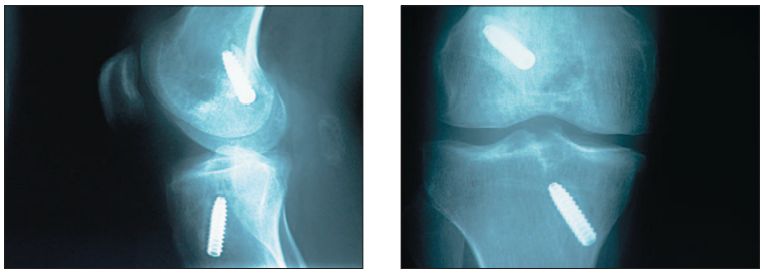

Zdjęcia radiologiczne pacjenta w 5 tygodniu po rekonstrukcji kolana po ponownym urazie skrętnym

Rtg pacjenta po rewizynej rekonstrukcji ACL z zastosowaniem allograftu